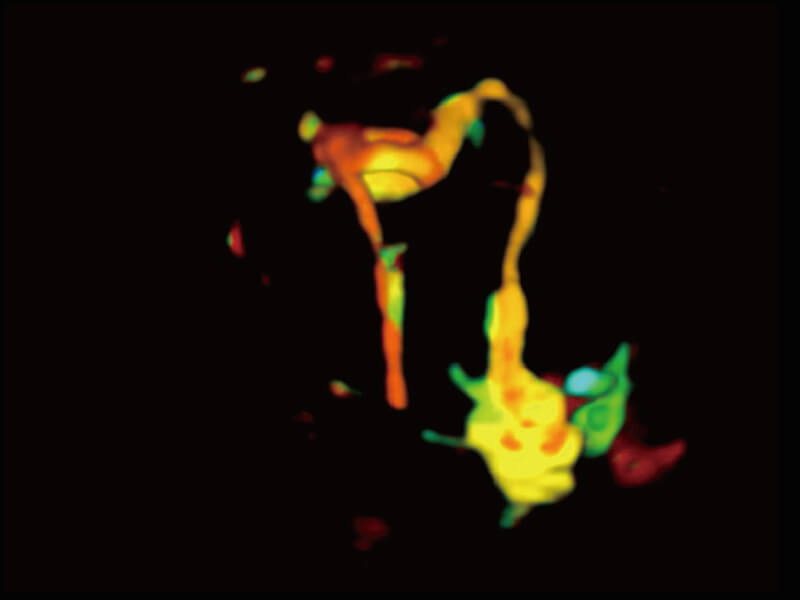

S60探头工艺,从前端信号处理每一个环节采集无损声学数据,真实还原组织原貌,再现解剖细节。